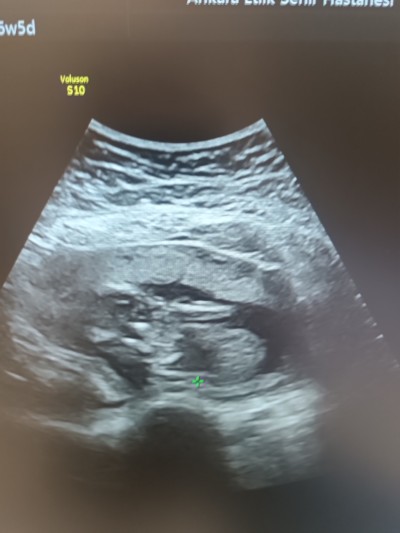

16+5 günlük kemik yapısına göre

image

kıza benziyor dediler. Aranızdan anlayan var mı?

Gebelik haftası 16+6

Tam kafasını net göstermemiş ama yuvarlak duruyor kız olma ihtimali yüksek galiba kuzum